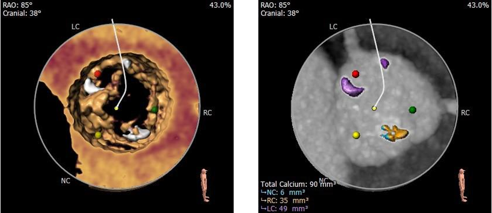

术前CT评估:

主动脉根部:

三叶式主动脉瓣,瓣环直径约22.5mm,LVOT呈收口型STJ、升主动脉内径可,非横位心,瓦氏窦较小。

冠脉测量:

左、右冠脉开口高度尚可,瓣叶长于冠脉开口下缘

钙化测量:

轻度钙化,左、无窦瓣叶纤维融合

入路测量:

股动脉入路可

风险评估:

• 三叶式主动脉瓣,瓣叶增厚,轻度钙化,收口型LVOT,锚定难度适中,存在瓣膜移位风险